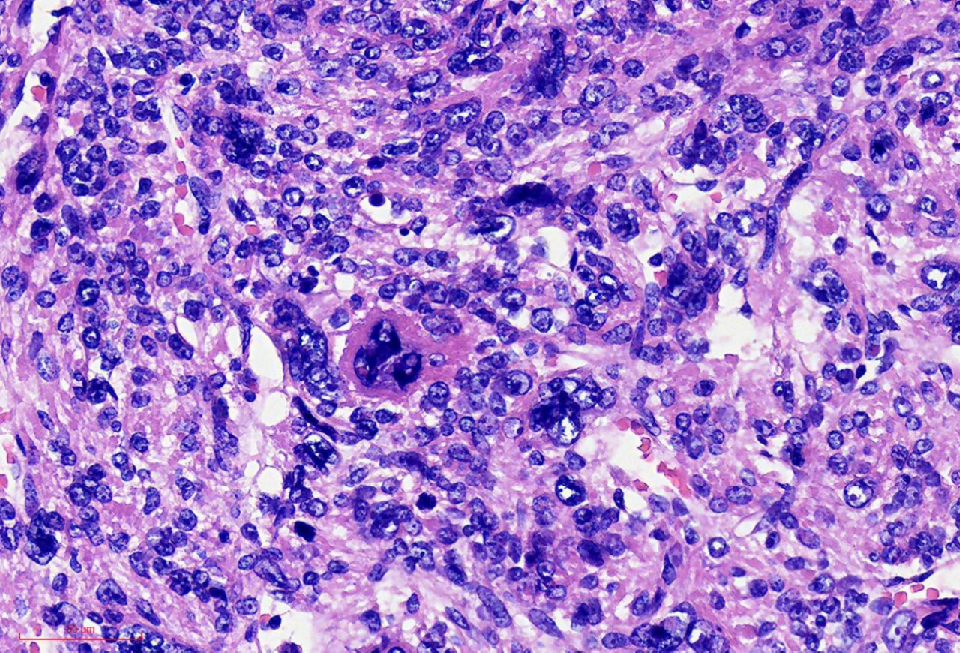

组织学改变

肿瘤与周围境界清楚

肿瘤细胞丰富

瘤细胞排列呈血管外皮瘤样

瘤细胞疏密相间

异型明显,可见核内包涵体,红核仁

未见凝固性坏死

核分裂象数2个/10HPF

肿瘤境界清楚

细胞丰富

鹿角样/血管外皮瘤样血管

肺水肿样水肿/疏密相间

细胞核奇异,嗜酸性胞质,有显著的嗜酸性核仁,核仁周围可见空晕,部分细胞呈横纹肌样

核分裂象少见

无凝固性坏死